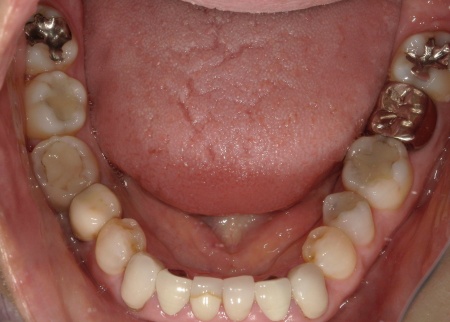

60代女性 古い被せ物を作り直して審美性を改善させた症例

「20年前、受け口を改善するために審美歯科で被せ物による治療を受けたが、仕上がりに不満が残った。最近、再び気になるようになったため、再治療が可能かを相談したい」とご相談いただきました。

拝見したところ、上下前歯には金属製の土台「メタルコア」を使用した被せ物(クラウン)が装着されており、被せ物と歯茎の境目付近が黒くなっていました。

また、保険適用の白い詰め物(コンポジットレジン)が充填されている部分には変色が見られます。ご自身の歯、被せ物、コンポジットレジン、それぞれの色調が異なっていることで審美性に影響が出ているため、上下前歯(合計12本)の被せ物と詰め物を新しくする必要があると診断しました。

また、左上前歯2本と左右下前歯2本は、細菌感染した神経を取り除いてから薬を詰める「根管治療」が施されていましたが、薬が歯根の先までしっかり詰められていなかったため、「再根管治療」が必要であることも併せてお伝えしています。